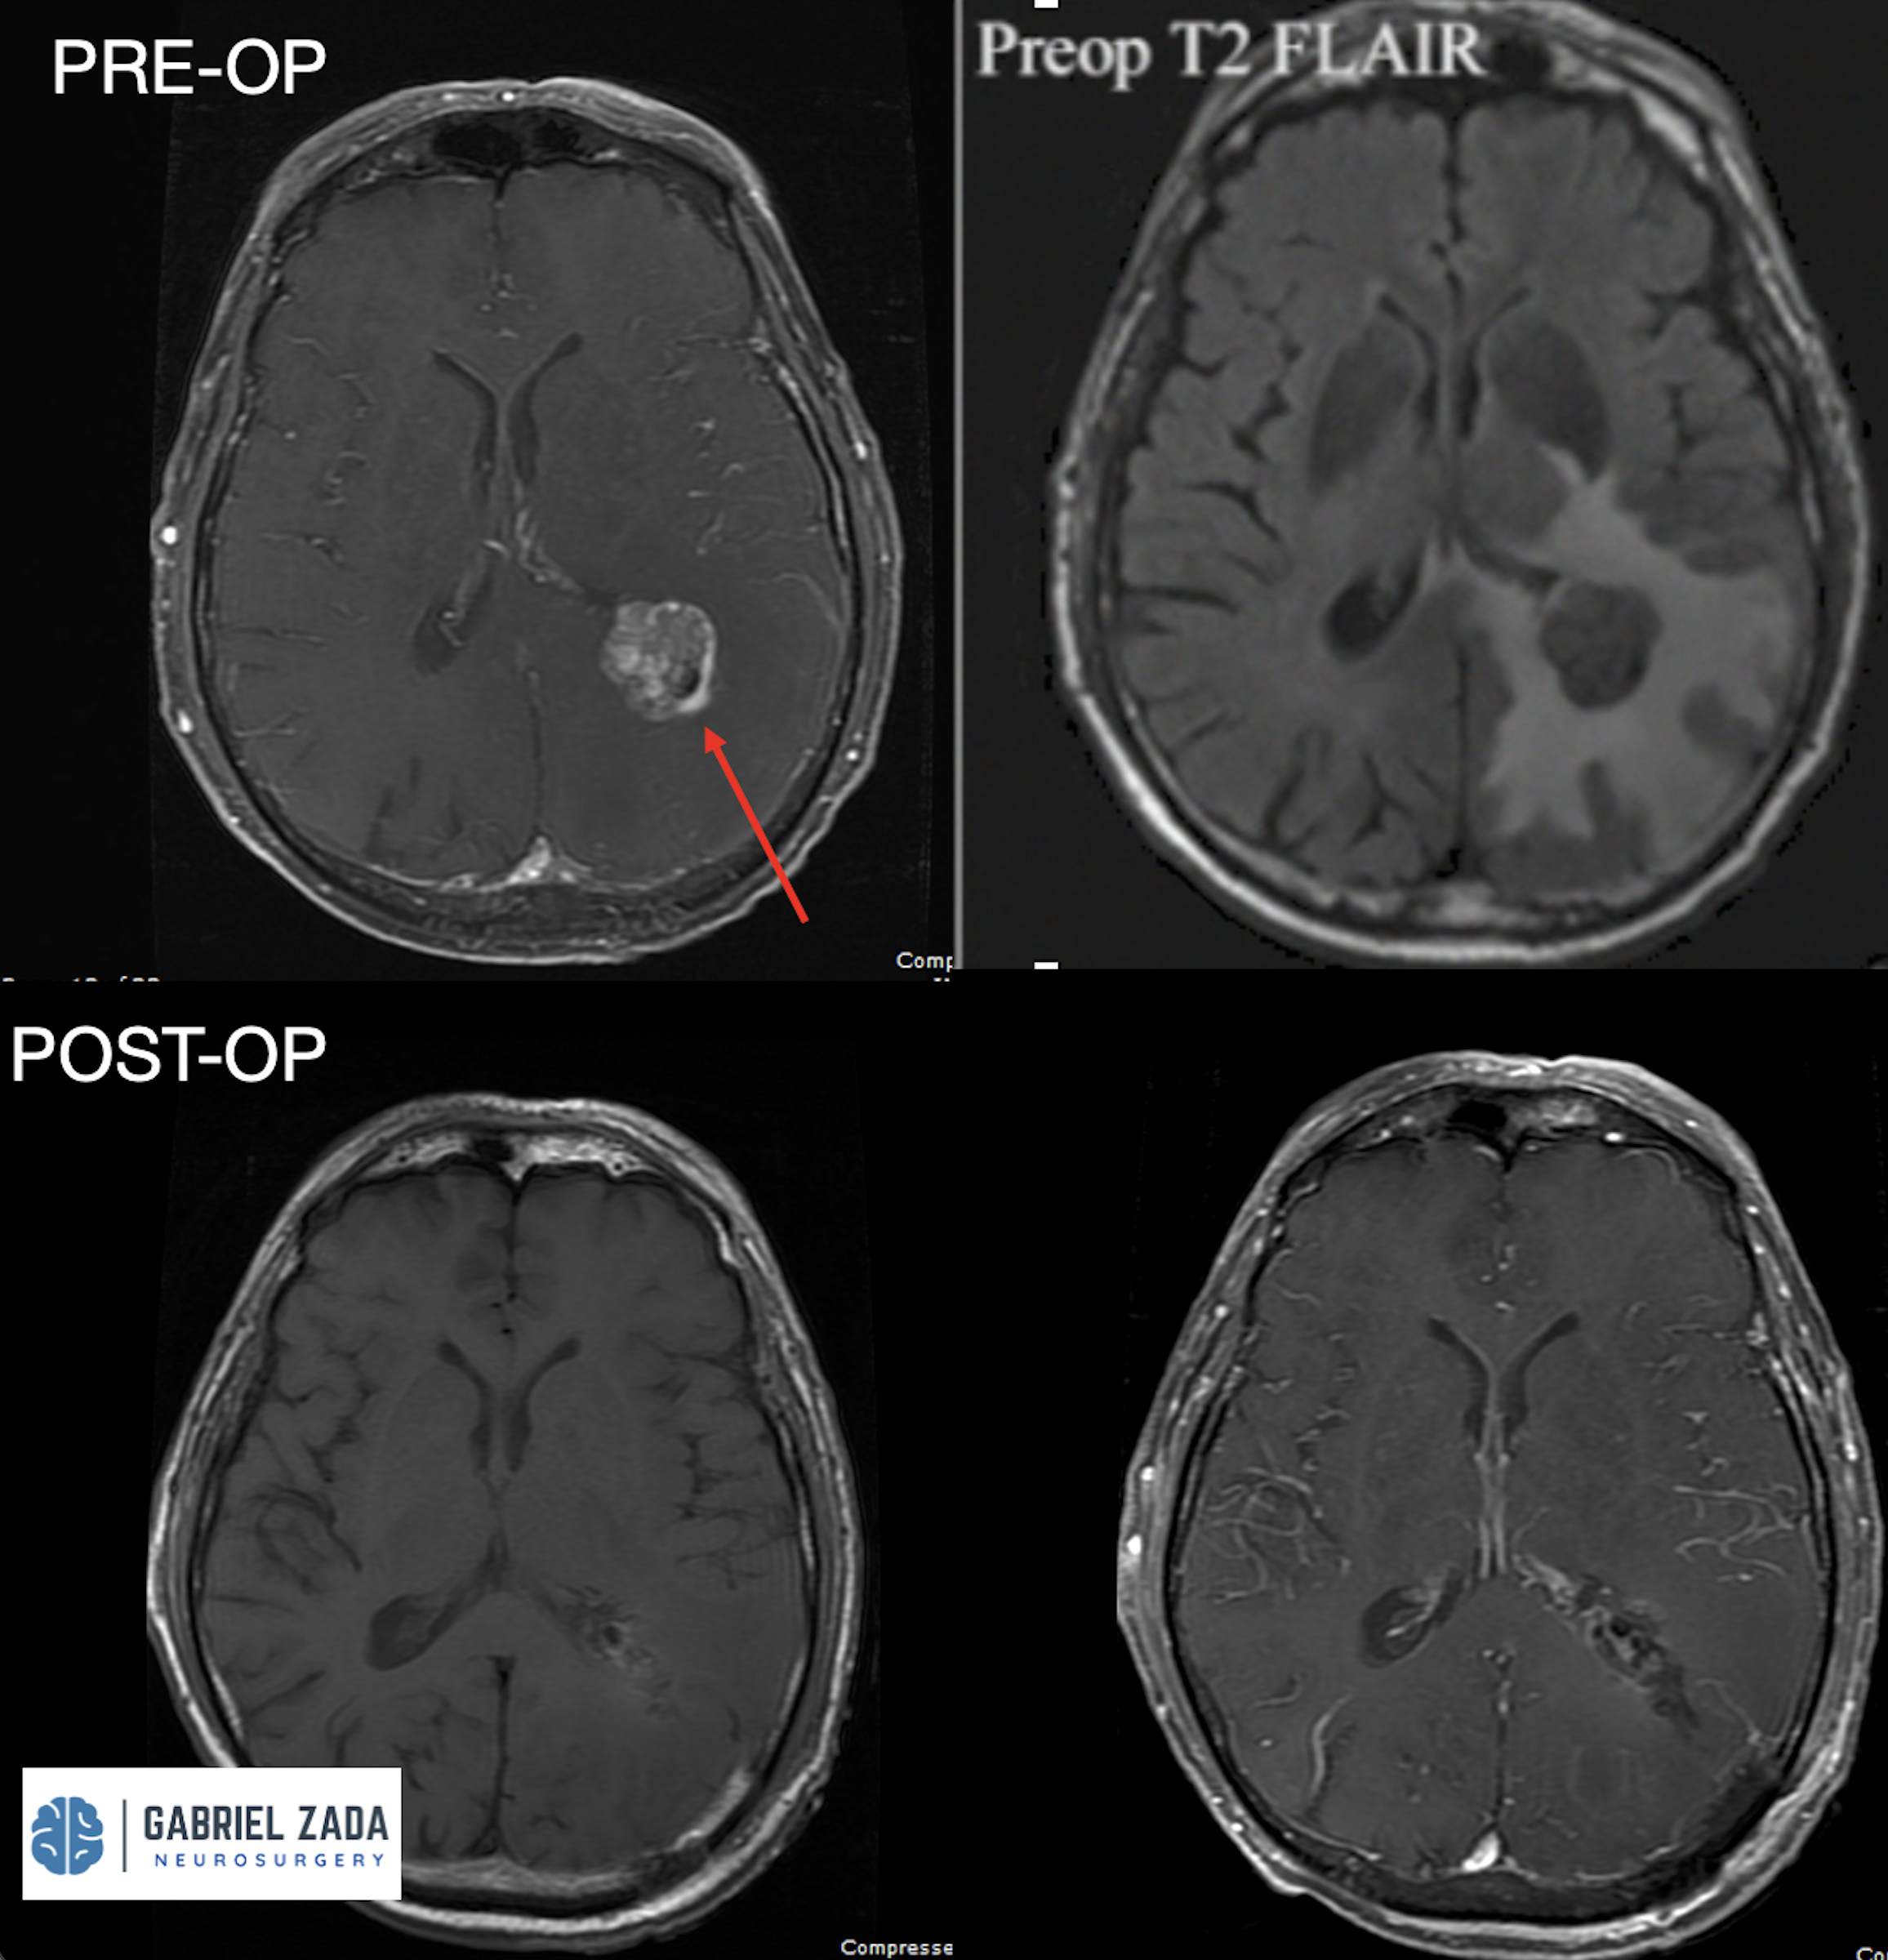

Explore this comprehensive gallery featuring pre‑ and post‑operative imaging of patients with skull‑base tumors treated by Gabriel Zada, MD, MS, FAANS, FACS. These cases highlight Dr. Zada’s expertise in advanced neurosurgical techniques and outcomes.

*Representative cases shown for educational purposes. All images de-identified. Individual results vary.